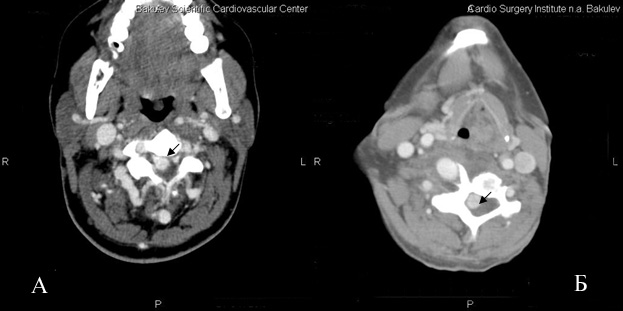

Правая позвоночная артерия после отхождения от подключичной артерии отклонена несколько вправо, идет назад, делая S-образный изгиб загрудинно резко неравномерно расширяется до 25 мм, далее расширенная артерия «делает» петлю, образуя мешковидное сосудистое образование распространяется вниз в грудную клетку до правой ветви легочной артерии, вверх до С5, размерами 87×40 мм. После образования петли позвоночная артерия по передней поверхности тела позвонка сужается до 10 мм, идет косо вниз и вправо, затем снова расширяется до 27 мм и на уровне С6 входит в позвоночный спинномозговой канал (рис.1,4). Дистальнее правая позвоночная артерия расширена и извита, в позвоночном канале соединяется с резко расширенными корешковыми ветвями и также резко расширенной правой спинальной артерией (спинной мозг оттеснен влево и кзади) (рис.3). Отмечается выраженная деформация поперечного отростка С6 справа, обусловленная длительной компрессией расширенными сосудами.

Рис.3 Аксиальный срез.

А- до процедуры. Резко расширены сосуды в спинномозговом канале (указаны стрелкой), сдавление спинного мозга.

Б- после процедуры.